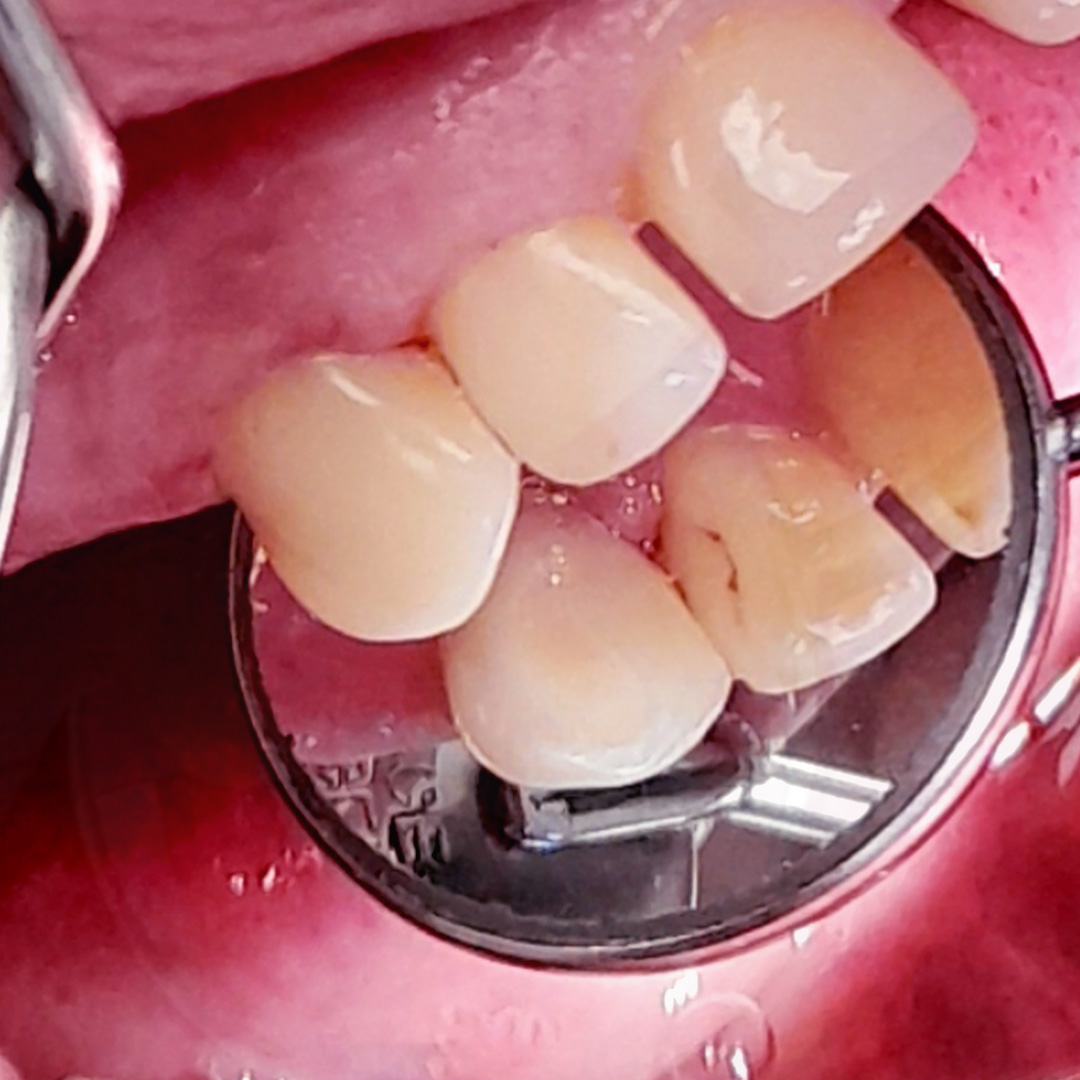

До и после лечения

- постановка постоянной пломбы из композита во второе посещение;